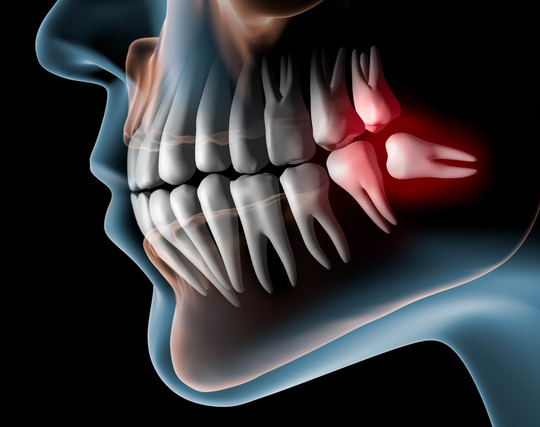

日本人の場合、あごのサイズがやや小さいため、生えてきても収まり切らず、邪魔者となってしまうことが多い。 結果、細菌の温床になり、周囲の歯ぐきを腫らしたり、ムシ歯になったりのトラブルメーカー。

6歳に生える第一大臼歯(6番、6歳臼歯)、12歳ごろ生える第2大臼歯(7番、12歳臼歯)に続いて、その奥に生えてくる大臼歯(8番)です。

親知らずのトラブルの原因やその症状

痛みが全く無いときでも、多くの人でその周囲がバイキンの棲み家になっている事実!

だからムシ歯になったり、歯肉が腫れたりする。

歯ブラシが届かない。 自覚症状が無いから、そもそも届かせようと突っ込んでもいない。 たとえ工夫しても凹み・窪みに届かない。